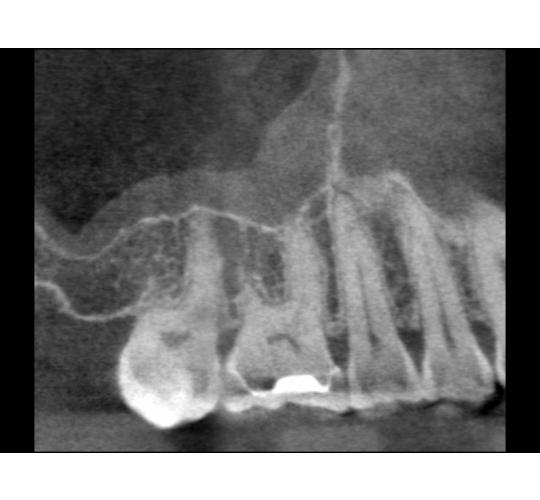

CBCT Diagnosis: Case #7

This patient has sinus problems on and off for the past year. He had 3 rounds of antibiotics as treatment along with nasal rinses and nasal sprays. Eventually they were referred for evaluation of his teeth. The tooth most probably became necrotic after the crown preparation but there were no perceived dental pain. He was eventually referred since the radiograph finally reveled a radio lucent finding. The CBCT shows how the sinus membrane actually has been affected. After endodontic treatment the sinus membrane usually returns to normal.